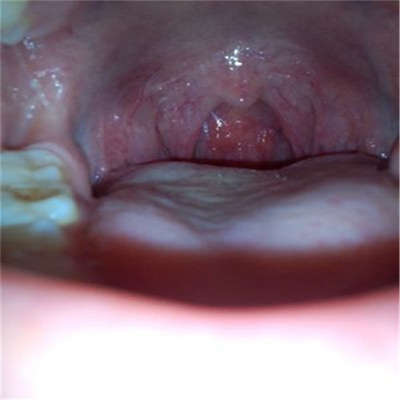

扁桃體惡性腫瘤圖片

扁桃體癌圖 (69)